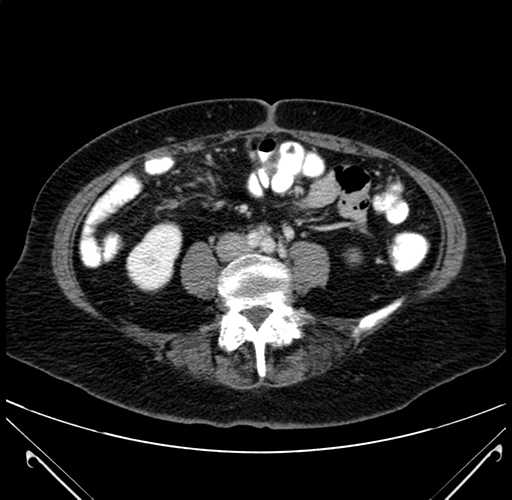

Axial Venous